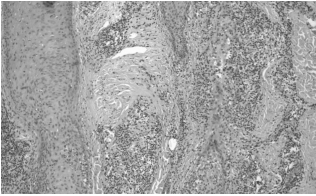

Первичные высыпания фолликулярного красного плоского лишая гистологически представлены в виде перифолликулярного лимфоцитарного инфильтрата на уровне фолликулярной воронки и перешейка наряду с вакуольной альтерацией клеток наружного волосяного влагалища и клиновидным гипергранулезом в устье пораженного волоса. В более длительно существующих случаях визуализируются перифолликулярный фиброз и атрофия эпителия на уровне фолликулярной воронки и перешейка, что представлено в характерной конфигурации «песочные часы». При длительно существующих случаях на месте алопеции определяются вертикально ориентированные эластические волокна, которые заменяют разрушенные волосяные фолликулы.

Аналогичную гистологическую картину мы получили и в нашем случае. Это терминальная стадия рубцовой алопеции без волосяных фолликулов, что позволяет поставить диагноз «псевдопеллада Брока» [13] (рис. 6–10).

Также при проведении патоморфологического исследования биопсийного материала было выявлено следующее: очаговый гиперкератоз, неравномерный гипергранулез, отек в шиповидном слое, вакуольная дистрофия клеток базального слоя, полосовидные или периваскулярные инфильтраты в верхних слоях дермы. Выявленные гистологические изменения более всего соответствуют красному плоскому лишаю, фолликулярной форме.

Рис. 6. Лимфогистиоцитарные инфильтраты вокруг волосяных фолликулов в их истмической зоне с их атрофией в виде «песочных часов» (слева). Рубцовая атрофия (справа) с полным исчезновением волосяных фолликулов и сальных желез. Мышцы, поднимающие волос, сохранены. Окраска гематоксилином и эозином, ув. ×40

Рис. 7. Тот же препарат, левая часть, ув. ×100

Рис. 8. Тот же препарат, правая часть, ув. ×100